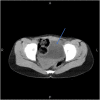

Case presentation: a 13-year-old female who experienced recurrent pelvic pain, dysmenorrhea, and abdominal mass for one month. We could not obtain the MRI as it was unavailable in our hospital, and the patient cannot afford its expensive cost in a private center. Instead, US showed an absent right kidney and doubled uterus with a heterogeneous cystic formation. A pelvic CT scan revealed an absent right kidney, an enlarged left kidney, a double uterus, and a left hematocolpos. We established the diagnosis of Herlyn-Werner-Wunderlich syndrome and started planning for correcting the anomalies via laparotomy.